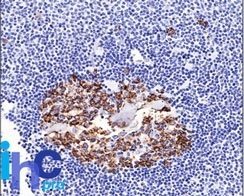

CDw75 Monoclonal Mouse Antibody (LN-1)

识别神经氨酸酶敏感性唾液酸蛋白 (CDw75),存在于生发中心 B 细胞和衍生淋巴瘤的细胞膜和细胞质中。这种 MAb 与骨髓的 RBC 前体、肾、乳腺、前列腺、胰腺、肺的导管和纤毛上皮细胞发生反应,并与淋巴细胞为主的霍奇金病中的胶质母细胞瘤、星形细胞瘤和 Reed Sternberg 细胞发生反应。它被证明是一种有助于确定已知淋巴组织中 B 细胞表型的抗体。